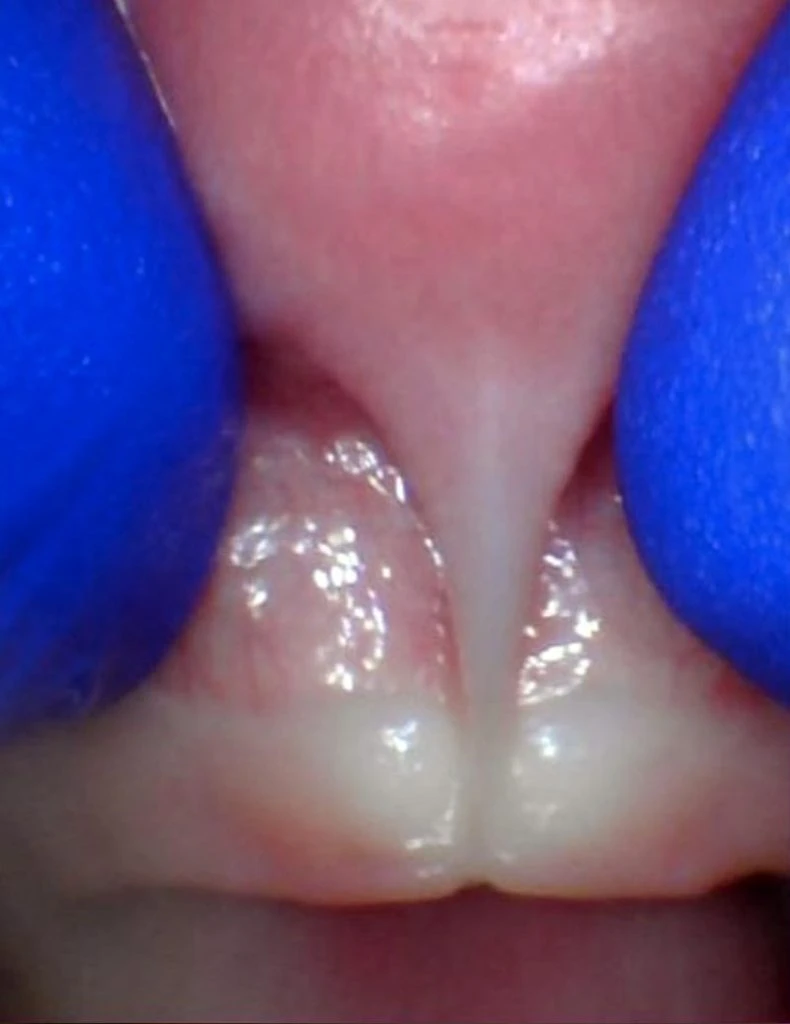

These images show the spectrum of tongue restriction in an infant.

View tongue restrictions

These images show the spectrum of posterior tongue restriction in an infant.

View posterior tongue restrictions

These images show the spectrum of tongue restriction in a child.

These images show the spectrum of posterior tongue restriction in a child.